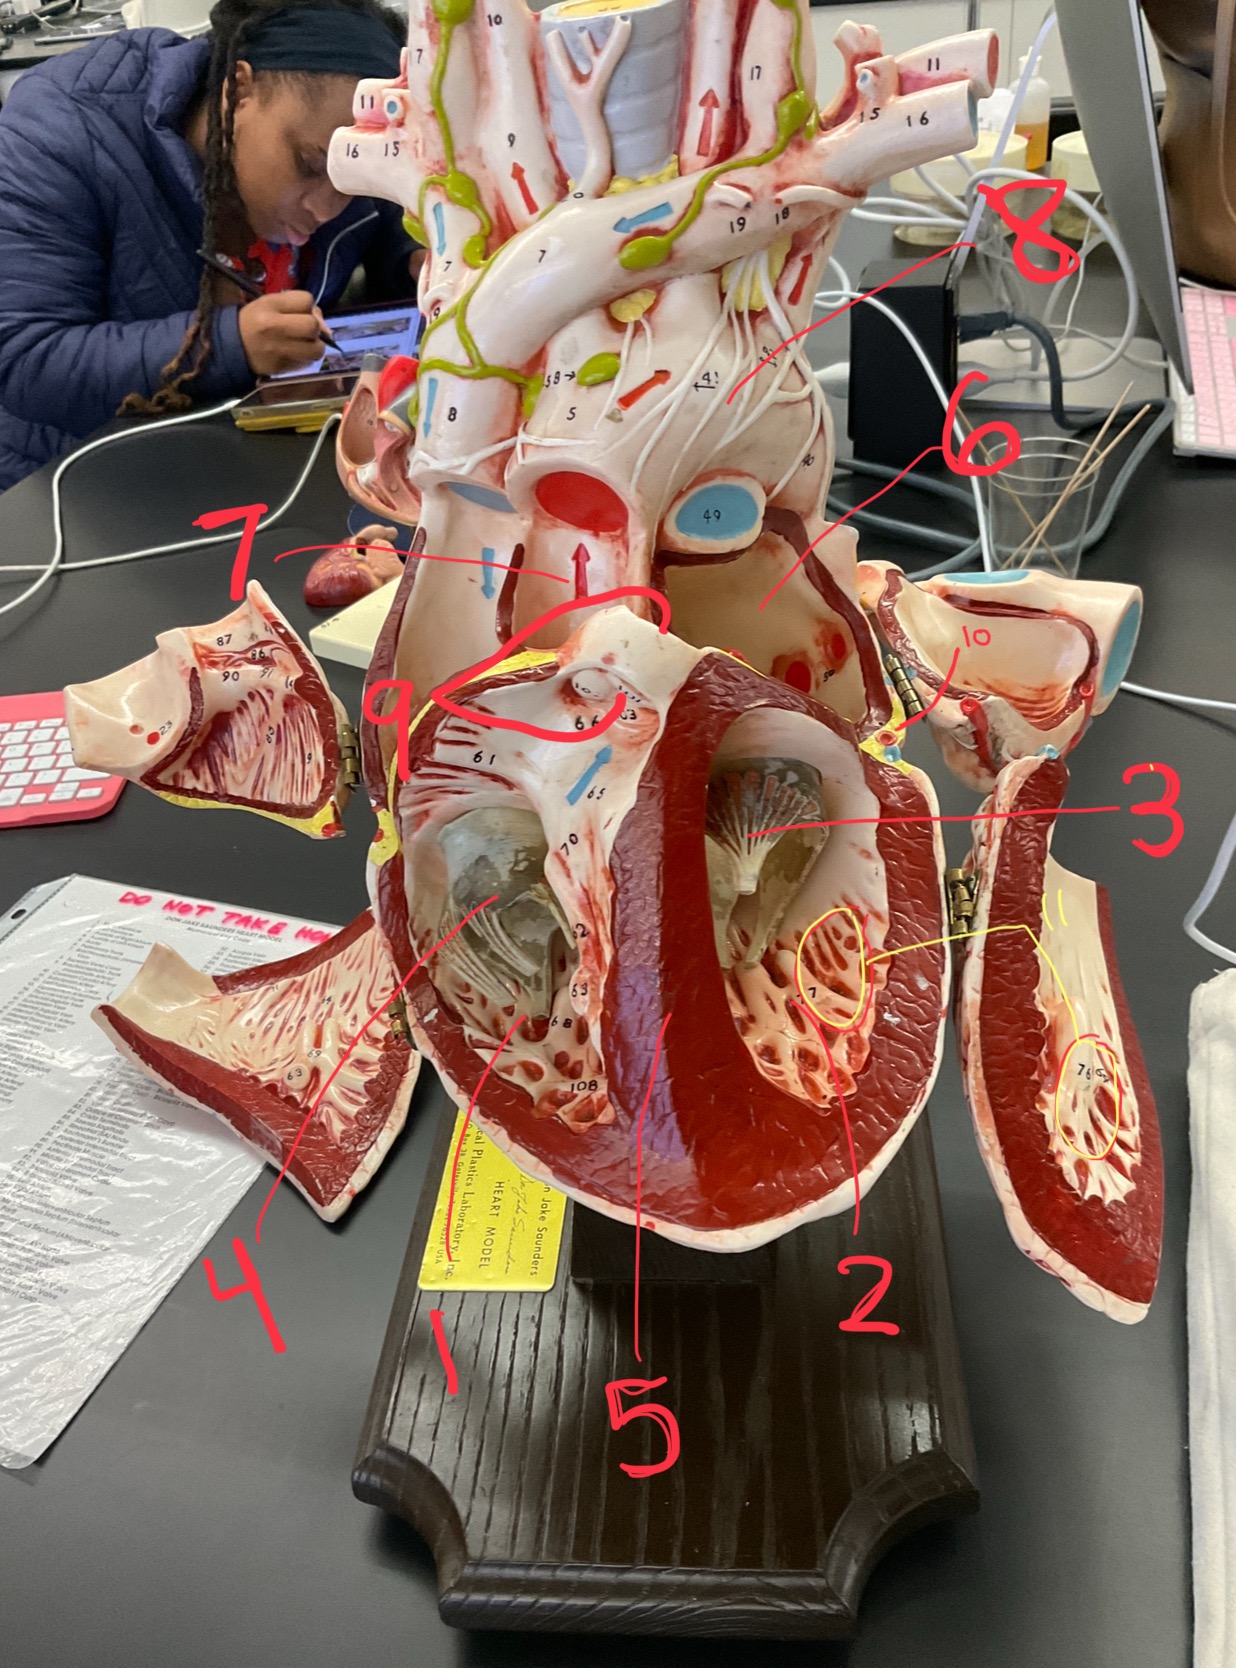

1

epicardium

2

3

endocardium

3

2

myocardium

4

1

coronary sinus

5

2

inferior vena cava

6

3

superior vena cava

7

1

right ventricle

8

2

left ventricle

9

3

bicuspid

10

4

tricuspid

11

5

interventricullar septum

12

6

left atrium

13

7

aorta

14

8

aortic trunk

15

9

pulmonary semi-lunar valve

16

10

atrevoventricullar sulus

17

11 (not smooth part)

trubeculae carneae

18

1

papillary muscle

19

2

chordae tendineae

20

4

pulmonary trunk

21

6

aortic trunk